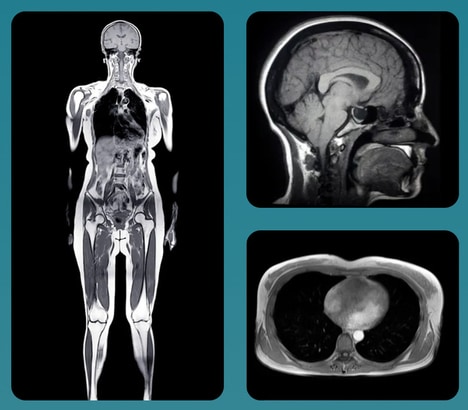

Trend - Full-body preventive scans, from MRI and CT imaging to 3D body composition analysis and at-home biometric monitoring, are expanding rapidly in the private wellness market. These services promise early detection of serious conditions like cancer and cardiovascular disease, while also providing detailed data on body composition, muscle decline, and longevity markers.

1. Proactive Health Monitoring — An increasing interest in proactive health monitoring reflects consumers' desire to take charge of their wellness by utilizing cutting-edge technology for early disease detection and health optimization.

Rapid MRI Scan Services

Springbok Analytics Gives New Insights into One's Wellness and Health

Enhanced Personalized Health Services

Keyspan and Prenuvo Partner to Offer MRI Scans